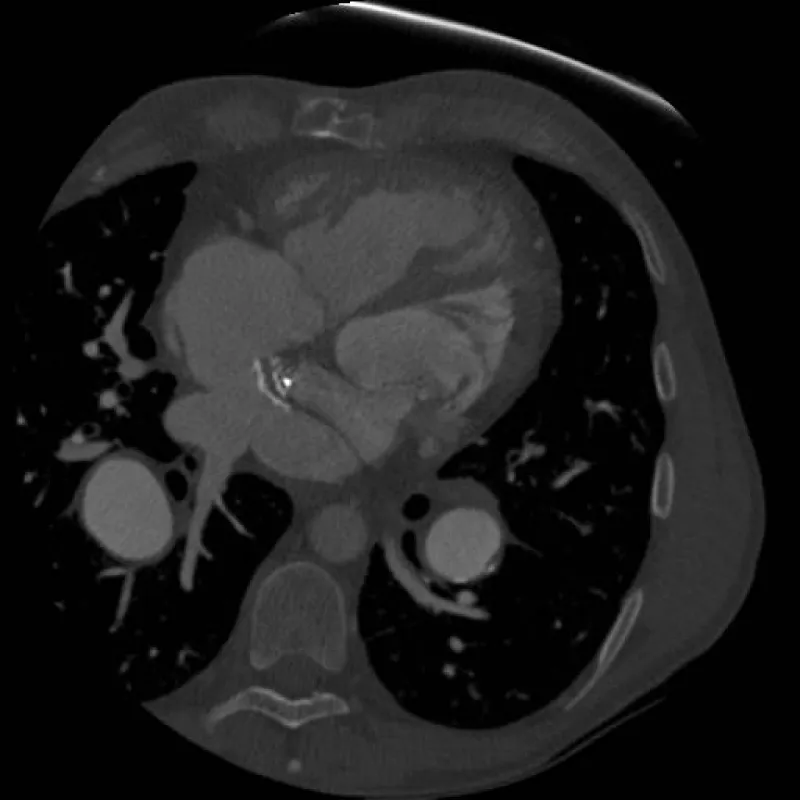

Cardiac catheterization (Table 1) demonstrated severe pulmonary hypertension with mean pulmonary artery pressure of 64 mmHg and a 16 mmHg gradient between pulmonary capillary wedge pressure (PCWP) and his RV (systemic ventricle) end diastolic pressure. He was not vasodilator responsive. Echocardiography and initial catheterization findings raised concern for baffle obstruction causing severe fixed pulmonary hypertension as a means to explain the documented gradient. In addition to his known underlying elevated pulmonary vascular resistance (PVR). He underwent re-intervention using a Brockenbrough technique to directly access the pulmonary venous baffle, confirm a baffle gradient with the intention of stenting the obstructed baffle. During this second catheterization, direct pressure measurements of the pulmonary venous baffle revealed no discrete baffle stenosis. It showed that there was no pressure gradient from the pulmonary veins to the tricuspid valve. Rather, direct pressures measurements revealed that direct A wave pressure in the baffle was 23 mmHg and commensurate with the RV end diastolic pressure (RVEDP), while the V wave was greatly elevated to 35 mmHg (tricuspid regurgitation was trivial by transesophageal echocardiographic assessment). Given the echocardiographic appearance of mild narrowing, the area in question was balloon-dilated without waist formation seen on angiography. Instead the neo left atrium was deemed rigid and undersized. Taken together, pulmonary hypertension with a large PCWP to RVEDP gradient, in the absence of a discrete hemodynamically significant obstruction, and with very large V waves in direct pressure measurement of the pulmonary venous baffle raised the concern for a diffusely stiff and calcified chamber with very poor compliance as the primary cause of his severe pulmonary hypertension. To confirm this diagnosis, the patient underwent a cardiac gated CT angiogram of the chest (Figure 1). CT showed the pulmonary venous baffle was patent but heavily calcified. Using cine imaging, the entire atrial/baffle complex was noted to be essentially non-compliant and moved en bloc with the beating ventricles.

Figure 1: CT image demonstrating heavily calcified pulmonary venous baffle. Calcification is heaviest on the baffle’s anterior aspect at the level of the systemic and pulmonary venous baffle crux.

We describe two patients with diffuse and heavy pulmonary venous baffle calcification resulting in a stiff, non-compliant neo-left atrium and pulmonary hypertension greater than 30 years post-Mustard procedure for D-TGA. In patient 1, we describe the phenomenon from a hemodynamic standpoint (mixed arteriolar and non-arteriolar pulmonary hypertension with very large baffle V waves and no discrete obstruction across the baffle), as well as cardiac-gated CT confirmation (heavily calcified, non-compliant baffle that moves en bloc with the beating ventricle). In patient 2, we re-demonstrate the hemodynamic characteristics of this phenomenon, and though her surgery was ultimately undertaken due to a complication of cardiac catheterization, the revision of her pulmonary venous baffle with neo-left atrial enlargement and subsequent complete resolution of symptoms, serves as proof-of-concept that this degree of chamber non-compliance is causative of severe symptomatology and surgery can be curative. We believe that without baffle enlargement that patient 2 would have suffered continued symptoms similar to those prior to their catheterization.